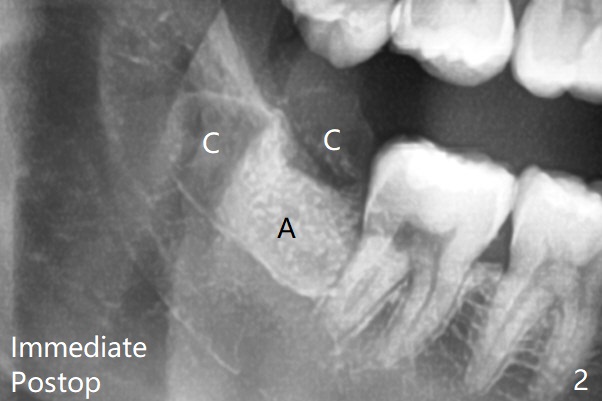

With 1/2 of Collagen plug placed in the apical portion of the socket, Bond Apatite (1 cc, A) is placed, followed by the other 1/2 of Collagen Plug coronally (Fig.2).